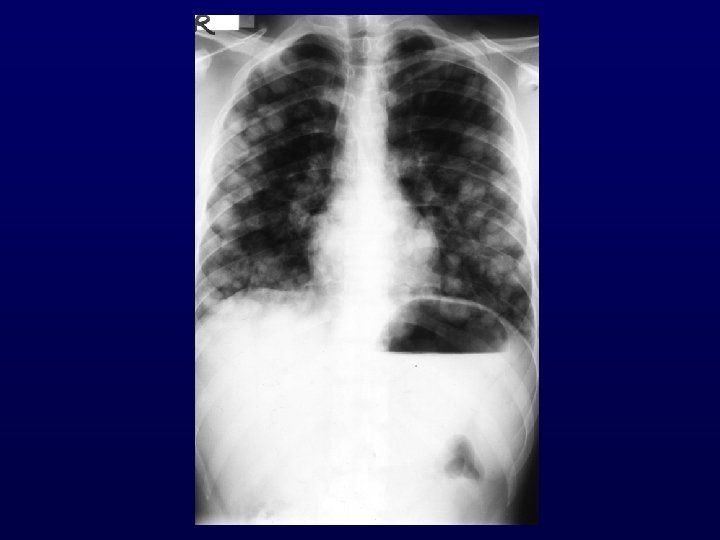

SQUAMOUS CELL CANCER INVOLVING CERVICAL LYMPH NODES Treatment : • • As locally advanced head-neck cancer. Surgery alone is inferior except p. N 1 neck disease with no extracapsular extension. • Radiation : both sides of neck and mucosa (entire pharyngeal axis and larynx). • Chemotherapy remains undefined (despite encouraging results with Platinum-based). Survival : • 5 -year survival 35– 50%. • Documented long term disease – free survivors.